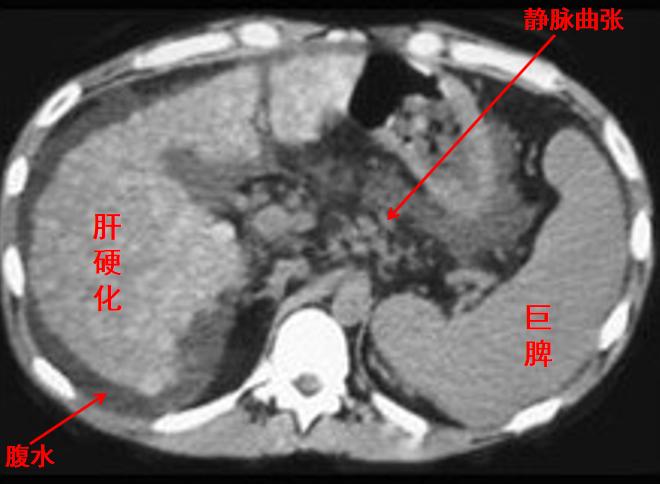

肝硬化患者CT图像,可见脾脏明显增大

肝炎后肝硬化是我国民众脾亢的最常见原因之一,其它的病因有慢性感染如疟疾、血吸虫病,肝炎病毒感染、结核等细菌感染、立克次体感染,类风湿性关节炎、系统性红斑狼疮、嗜酸性颗粒细胞增多症、脾淀粉样变性、特发性血小板减少性紫癜、真性红细胞增多症、地中海地贫血,充血性心力衰竭,恶性淋巴瘤及急慢性淋巴细胞性白血病等,均可引起继发性的脾大、脾功能亢进。

医生根据李大姐脾脏增大,同时又伴有血中红细胞、白细胞、血小板减少,即有所谓的“全血细胞减少”或“血细胞三系降低”,基本上就认定了“脾亢”的诊断。再结合她有肝炎、肝硬化的病史,又排除了其它引起脾肿大和血细胞减少的疾病,脾亢诊断也就确立了!